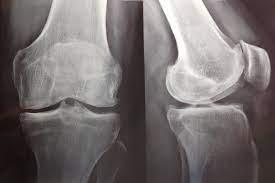

Discrepancia de miembros inferiores en artroplastia total de rodilla. ¿Es realmente un problema?

La incidencia de discrepancia de longitud de miembro inferior tras el con reemplazo total de rodilla fue del 30%. No se requirió  intervención como consecuencia de dicha discrepancia. Los resultados funcionales y dolor al seguimiento alejado no demostraron diferencias entre ambos grupos. Rev Fac Cien Med Univ Nac Cordoba , 16 de septiembre de 2022